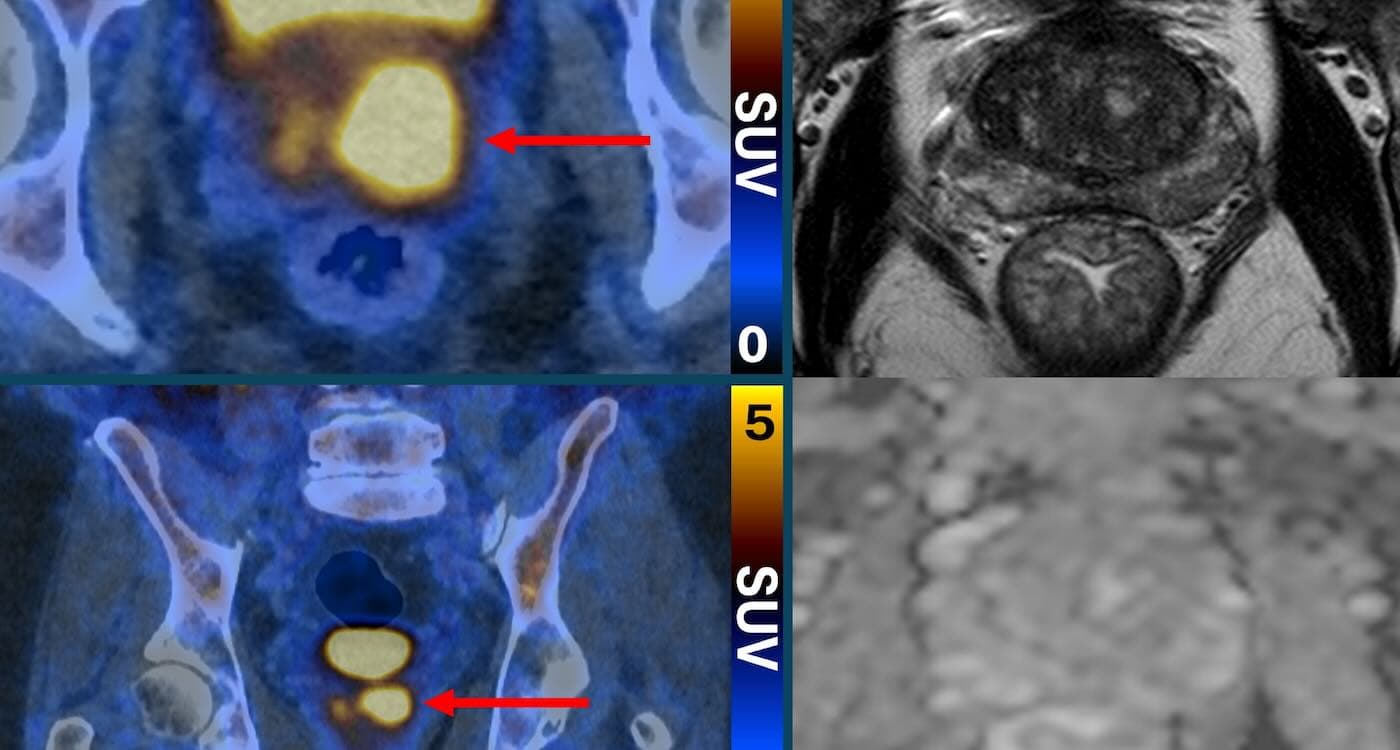

Im Zentrum dieser medizinischen Revolution steht der sogenannte PSMA-PET/CT-Scan. Hierbei handelt es sich um ein hochmodernes bildgebendes Verfahren, das zwei Technologien kombiniert: die Positronen-Emissions-Tomographie (PET) und die Computertomographie (CT). Der entscheidende Durchbruch liegt in der Verwendung eines speziellen radioaktiven Markers, einer Substanz, die an ein Molekül namens Prostata-spezifisches Membranantigen (PSMA) andockt. Dieses PSMA findet sich in hoher Konzentration auf der Oberfläche von Prostatakrebszellen, insbesondere bei aggressiveren Tumorarten.

Vor dem Scan wird dem Patienten dieser Marker injiziert. Er verteilt sich im Körper und bindet gezielt an die Krebszellen. Während des Scans werden diese angereicherten Zellen dann sichtbar und leuchten auf den Bildern hell auf. „Es ist selten, eine so starke Bildgebung zu sehen, die in der Klinik so aussagekräftig sein könnte", erklärte Dr. James Buteau, ein Nuklearmediziner, der die entscheidende Studie leitete. Aggressive, potenziell gefährliche Tumore können so mit hoher Genauigkeit identifiziert werden, während harmlose oder sehr langsam wachsende Veränderungen unauffällig bleiben.

Für die Patienten, bei denen der Scan ein positives Ergebnis zeigte, bot die Technologie einen weiteren entscheidenden Vorteil. Die leuchtenden Markierungen auf den Bildern zeigten den Ärzten exakt, wo sich die verdächtigen Areale in der Prostata befinden. Die anschließende Biopsie konnte somit gezielt auf diese Bereiche ausgerichtet werden, was die Treffsicherheit des Verfahrens massiv erhöht und das Risiko von Komplikationen minimiert. Studien-Co-Leiterin Professor Louise Emmett sprach von einem „Gürtel-und-Hosenträger-Ansatz“, der zuverlässig zwischen gefährlichen und harmlosen Befunden unterscheiden könne.